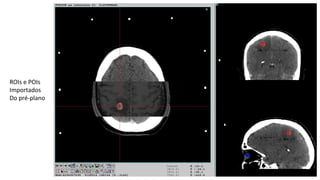

Na CT estereotáxica fazemos o registro e fusão com a MRI e depois importamos as ROIs e POIs.

ROIs e POIs

Importados

Do pré-plano